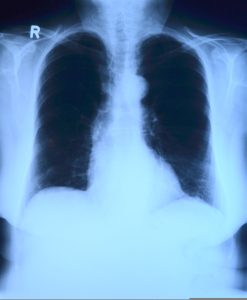

U Srbiji je prvi put urađena transplantacija pluća. Da li je ovo novi tračak nade za ljude koji čekaju da ponovo prodišu punim plućima

U Srbiji je prvi put urađena transplantacija pluća – zahvat koji do sada nije bio dostupan domaćim pacijentima, pa su oni kojima je bio potreban, morali na operaciju u inostranstvo.

Nova pluća dobio je pre nekoliko dana četrdesetdvogodišnji pacijent, koji se, prema rečima lekara, uspešno oporavlja. Operaciju su izveli hirurzi Klinike za grudnu hirurgiju Univerzitetskog kliničkog centra Srbije, u saradnji sa timom Medicinskog univerziteta u Beču.

„Sa velikim zadovoljstvom mogu da kažem da je uspešno obavljena prva transplantacija pluća u Srbiji. Iako dug put predstoji, pacijent se dobro oporavlja. Ovaj zahvat je plod dugog rada i sistematskih priprema“, izjavila je za RTS profesorka Maja Ercegovac, direktorka Klinike za grudnu hirurgiju.

Ona je naglasila da je čitav proces – od pripreme i procene pacijenta, preko operacije, do postoperativnog toka – razvijen po uzoru na transplantacioni program u Beču, sa kojim domaći lekari već sarađuju.

Transplantacija pluća je medicinski postupak u kojem se bolesno ili nefunkcionalno plućno tkivo pacijenta zamjenjuje zdravim plućima donora. Ovaj kompleksan zahvat se koristi kao poslednja opcija lečenja za pacijente sa teškim oboljenjima pluća koja ne reagiraju na druge terapije.

Najčešći razlozi za transplantaciju pluća su hronična opstruktivna bolest pluća (HOBP), idiopatska plućna fibroza, cistična fibroza i plućna hipertenzija.